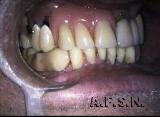

CASO REABILITADO POR PRÓTESE METALO-CERÂMICA SUPERIOR E PRÓTESE INFERIOR REMOVÍVEL SOBRE COROAS TELESCÓPICAS:

ANTES